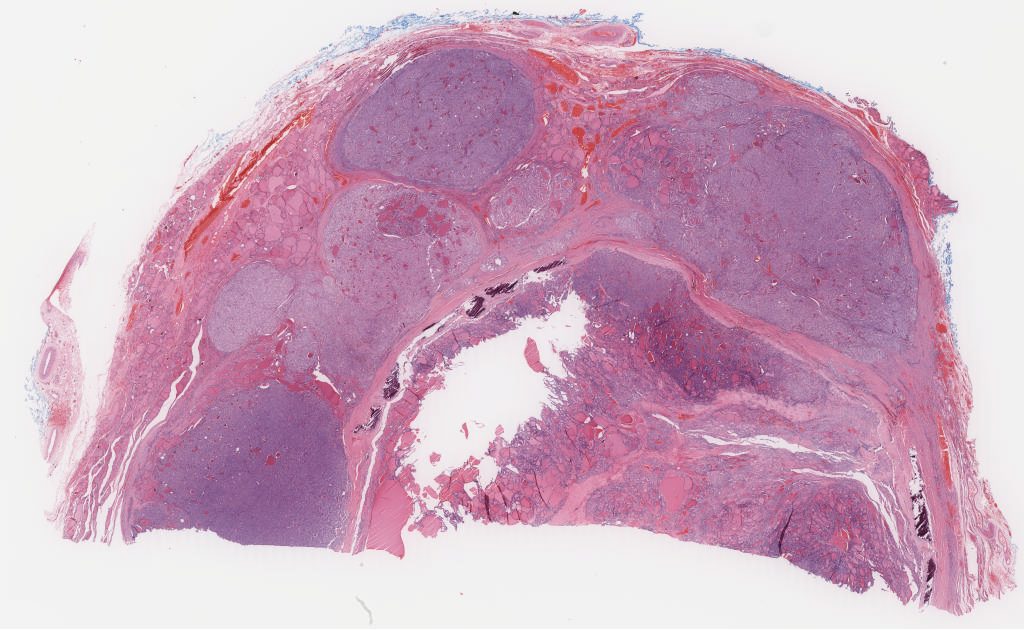

TSN 032.1.svs

100912

x

62003

@

40X